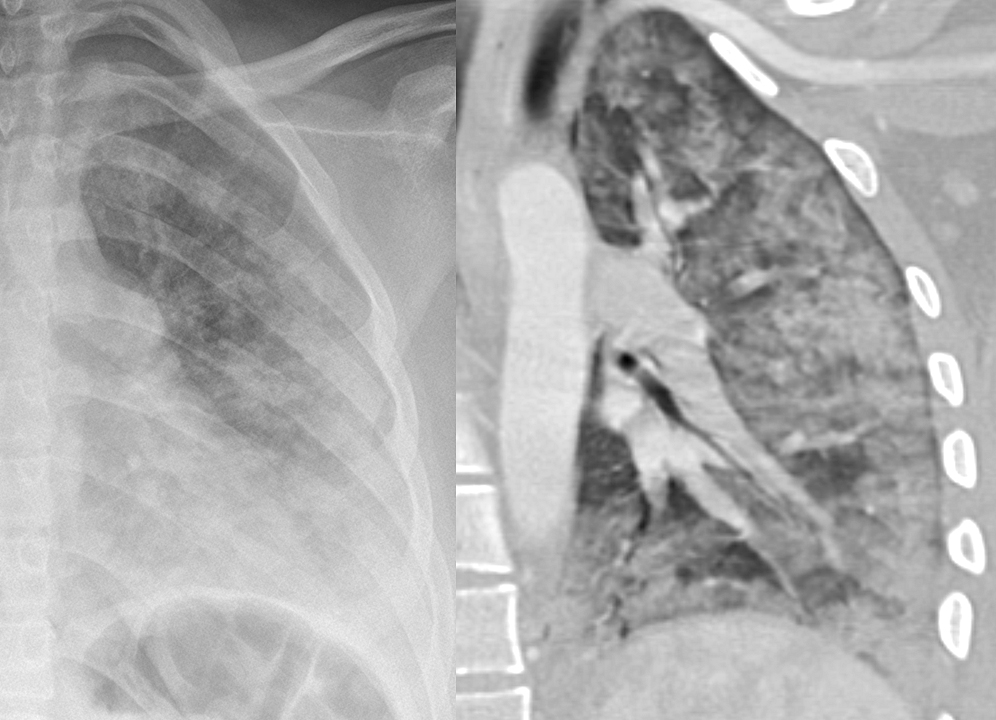

Gallery Blunt Chest Trauma Lung injury Contusion

Contusion